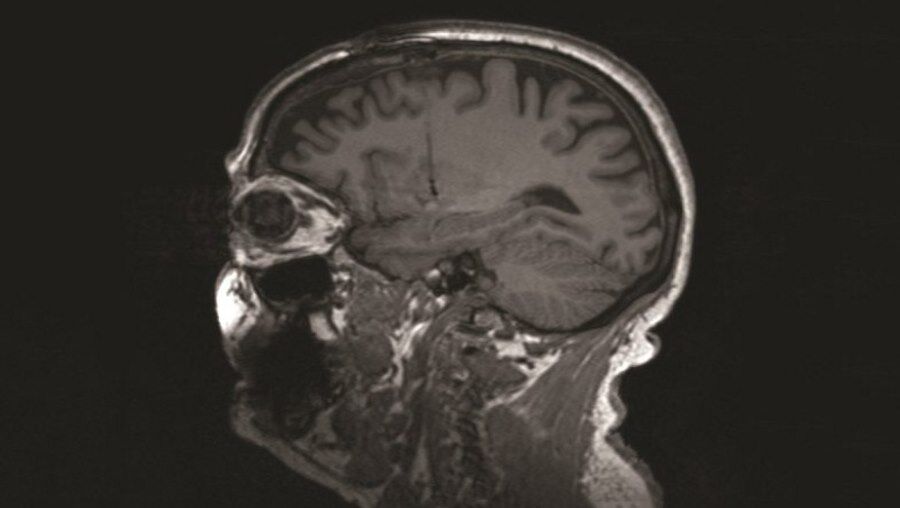

Naukowcy stworzyli „dekoder nastroju”, który może mierzyć depresję

Depresja to trudna i wyniszczająca choroba. Mimo wielu lat badań naukowcy wciąż nie wiedzą wszystkiego na jej temat. Choć wkrótce może to się zmienić. Amerykańscy naukowcy opracowali urządzenie nazwane „dekoderem nastroju”, dzięki któremu można odczytać stan emocjonalny ludzi na podstawie samej obserwacji aktywności mózgu. Uczeni mają nadzieję, że dzięki niemu uda się lepiej poznać tę chorobę.

Depresja jest poważnym i niezwykle złożonym problemem. Zmaga się z nią coraz więcej osób. W tym kontekście przynajmniej pewną pozytywna informacją jest to, że lekarze zapewne dostaną do rąk nowe narzędzie umożliwiające szybsze jej diagnozowanie, bo jak...